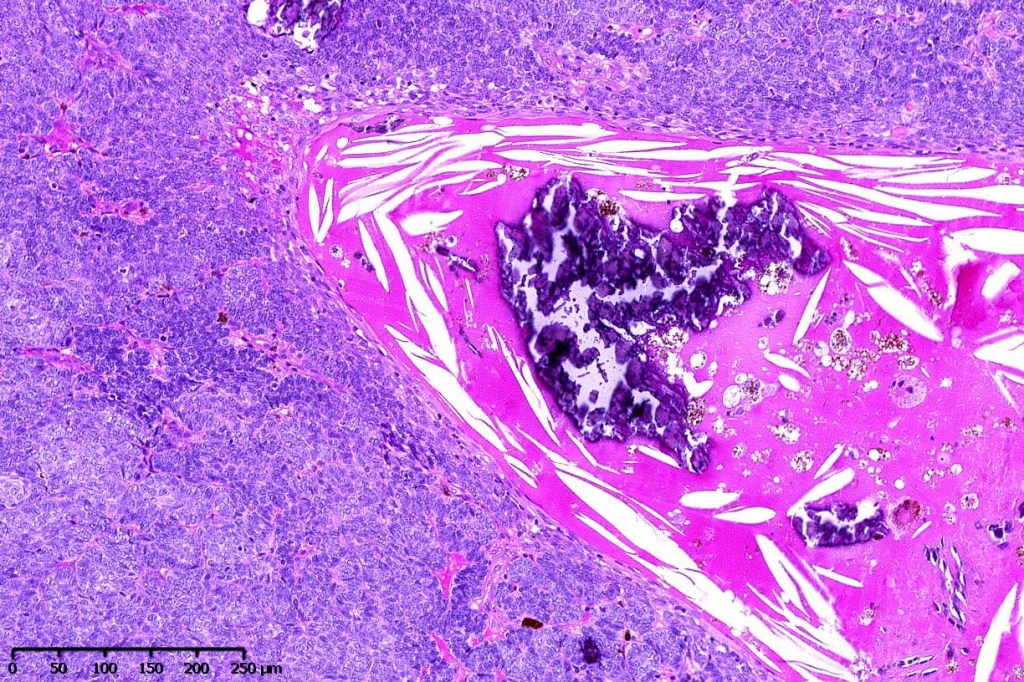

•Variable keratocysts

•Variable features include amyloid, focal granulomatous inflammation associated with free keratin & calcification